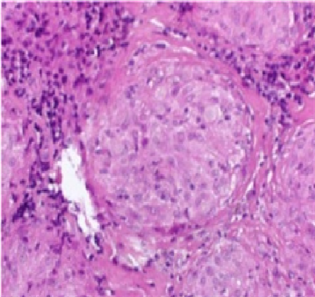

enlargement (red arrows) in the mediastinum). Gallium (68Ga) PET scan indicated multiple foci of increased uptake on mediastinum and axillae, highly suspicious to Sarcoidosis with Cardiac Involvement (Figure 3―Gallium PET scan showed multiple foci of increased uptake on mediastinum and axillae (black arrows)).The Final diagnosis of Sarcoidosis was established by mediastinal lymph node biopsy showing non-caseating epithelioid cell granulomas of sarcoidosis (Figure 4―Mediastinal Lymph node biopsy indicate noncaseating epithelioid cell granulomas (center of image) of sarcoidosis (H & E staining)).

Figure 4. Mediastinal Lymph node biopsy indicate noncaseating epithelioid cell granulomas (center of image) of sarcoidosis (H & E staining).